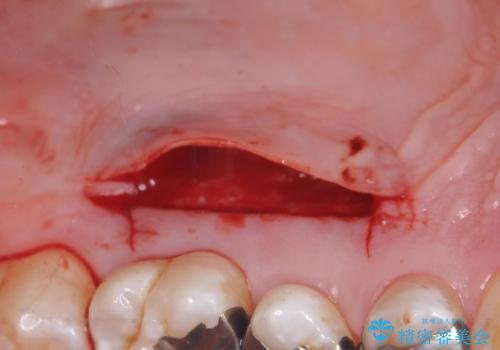

- 奥歯の歯茎が下がっていて(歯肉退縮)歯が染みるとのことで来院された患者様です。

退縮した歯茎に対して移植をすることで、しみる場所を覆う計画です。

歯根の分岐部よりも根尖側の頬側面が露出している状態でしたが、露出部位を分岐部までに抑えることができました。

しみる症状も改善され、大変喜んでいただけました。

術後は歯肉が下がらないよう経過を追っていきます。